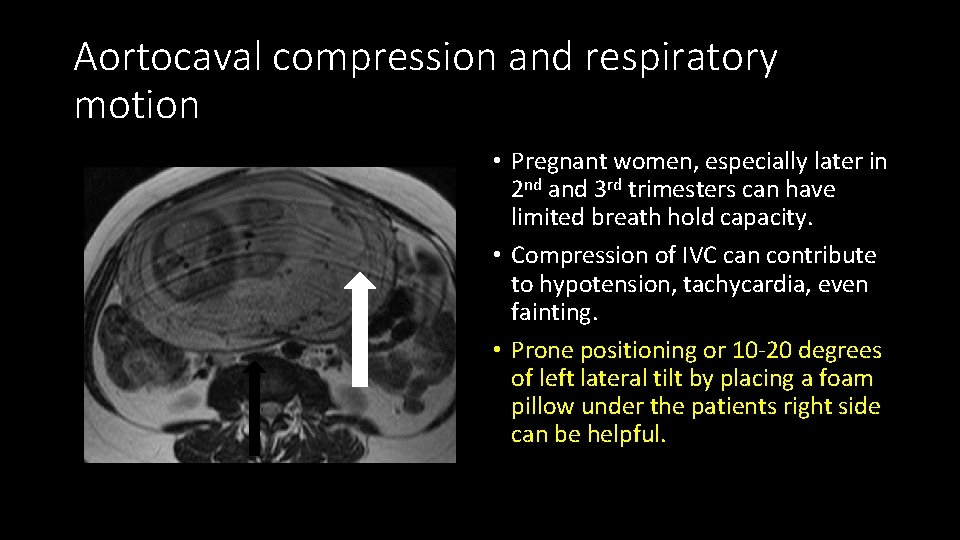

Aortocaval compression and respiratory motion • Pregnant women, especially later in 2 nd and 3 rd trimesters can have limited breath hold capacity. • Compression of IVC can contribute to hypotension, tachycardia, even fainting. • Prone positioning or 10 -20 degrees of left lateral tilt by placing a foam pillow under the patients right side can be helpful.